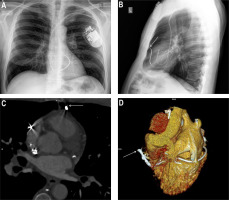

We present a case of a 59-year-old man referred to a tertiary cardiology centre for further investigation and treatment from a local hospital. He had a background of dilated cardiomyopathy. He underwent implantation of cardiac resynchronization therapy with a defibrillator (CRT-D) system in another hospital for secondary prevention of sudden cardiac death 18 months before (Figures 1 A, B). The patient reported an intermittent pricking sensation in the left side of the chest for the previous 12 months. The device interrogation showed unstable R-wave sensing values in the range 1.3–2.6 mV and gradually increasing stimulation thresholds on the right ventricular lead (RVL) for the previous 6 months. Impedance trends on all leads were within the normal range and stable. The patient had a single inappropriate shock due to lead noise, followed by right ventricular lead capture loss 2 weeks before the admission.

A, B – Chest X‑ray before the procedure. Lateral projection (B) view suggests a perforation of the heart by cardioverter-defibrillator lead Durata 7122Q65 located on the free wall of the right ventricle (arrow). C, D – Cardiac CT: MPR of right ventricle wall perforation (C) and VRT reconstructions of right ventricle lead perforation (D). Visible tip of the right ventricular lead adjacent to the border of the third bronchopulmonary segment and the lingula of the left lung, with no pericardial effusion or pneumothorax. Image of “dry” cardiac perforation through the cardioverter-defibrillator lead protruding beyond the myocardium by approximately 30 mm (C, D). Arrows indicate lead tip localized externally to the heart and pericardium

Chest X-ray was suspicious of cardiac perforation with a RVL (Figure 1 B). In transthoracic echocardiography, no increase in the pericardial fluid was observed. In cardiac computed tomography, the tip of the RVL was visible adjacent to the border of the third bronchopulmonary segment and the lingula of the left lung. There was no pericardial effusion or pneumothorax (Figures 1 C, D).

Lead perforations (LP) are rare (0.50%) but serious complications of cardiac implantable electronic device (CIED) implantation [1]. LP following CIED lead implantations are divided into acute (≤ 24 h), subacute (< 1 month), and delayed (> 1 month), according to their occurrence following implantation [2]. The rate of iatrogenic cardiac tamponade after CIED implantation is about 0.20% [3]. Delayed LP tends to present with lower rates of cardiac tamponade due to the self-sealing properties of the ventricular wall by muscle contraction, haemostasis, and subsequent fibrosis [4]. Risk factors for procedure-related iatrogenic cardiac perforation include apical or free wall placement of the RVL, over-torquing active fixation leads, and excessive lead slack as well as little experience of the operator [1]. The 2021 European Society of Cardiology pacing guidelines recommend placement of the lead in the mid-ventricular septum in patients at high risk of perforation, and the use of multiple fluoroscopic views to locate the lead in the right ventricle [5]. In this case, the most likely cause of the right ventricular free wall perforation was improper placement of an ICD lead on the free wall of the right ventricle combined with over-torquing its active fixation mechanism, which remained unrecognized during the implantation time (Figure 1 B).